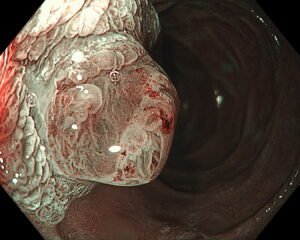

El estudio más útil para confirmar el diagnóstico y evaluar la severidad de la enfermedad es la endoscopía digestiva alta, que permite visualizar el esófago, detectar erosiones, úlceras o estrechamientos, y descartar otras enfermedades como la hernia hiatal.

Durante la endoscopía, se obtienen imágenes de alta resolución que ayudan a determinar el tratamiento más adecuado y monitorear la respuesta a la terapia.